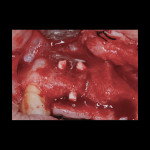

Antibiotic therapy (amoxicillin 1.5 g/day) was initiated 1 day prior to surgery. A crestal incision in combination with a vertical release on the mesial aspect of No. 11 permitted broad mucoperiosteal flap reflection. Small cortical perforations were created in the buccal plate at site Nos. 12 and 13 to increase vascularity at the augmented site. Osteotomies measuring 2 mm in diameter and 3 mm in depth stabilized two 7-mm long pins positioned to support vertical and horizontal bone growth. A small oval lateral window was created at site No. 14 for sinus augmentation (Figure 18). The ridge at site Nos. 12 and 13 was grafted with a 4:1 combination of Regenaform and bovine bone mineral (NuOss®, Ace Surgical Supply Co., www.acesurgical.com) and the sinus grafted with L-PRF and NuOss. The grafted sites were first covered with four L-PRF membranes (Figure 19), then two pericardium membranes (CopiOs® Pericardium Membrane, Zimmer Dental, www.zimmerdental.com), followed by the final layer of L-PRF.

Five months later, the CBCT revealed substantial horizontal and vertical augmentation along the entire extent of the ridge (Figure 20), thus permitting placement of three bone-level 4.1-mm x 10-mm implants (Straumann, www.straumann.us) (Figure 21). The implants were submerged and allowed to heal for an additional 4 months prior to uncovering and restoration (Figure 22 and Figure 23).